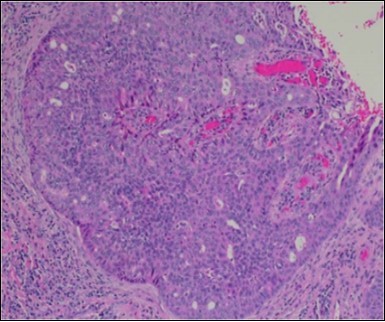

The neoplasm is composed of lobules of aberrant epithelial cells configured in cords with incrimination of the dermis and epidermis.. Malignant cells congregate within the epidermis or infiltrate the dermis, especially in the primary tumour. Tumour cells within tumour aggregates display a well demarcated cellular outline and appear distinct from encompassing squamous cells. Numerous tumour cell clusters demonstrate a cystic lumen. Prominent epidermal acanthosis is discerned on account of tumour cell proliferation 6, 7.

Granular arrangement of malignant cells and intercellular bridges are conspicuous with the demonstration of nuclear atypia, pleomorphism, prominent mitosis and tumour necrosis. A peripheral palisade is discernible within the cellular aggregates. Mitotic figures are common and can be quantified as up to 12 mitosis/ high power field. Tumour differentiation can prominently be of the ductal category with the demonstration of intra-cytoplasmic lumina. Comedo type tumour necrosis is evident along with foci of squamous differentiation The neoplasm is reactive to periodic acid Schiff ‘s (PAS) stain. (Figure 1, Figure 2, Figure 3, Figure 4, Figure 5, Figure 6, Figure 7, Figure 8, Figure 9, Figure 10, Figure 11, Figure 12, Figure 13.

Figure 3.Cohesive accumulations with numerous ductular articulations of carcinoma cells in eccrine porocarcinoma (15).